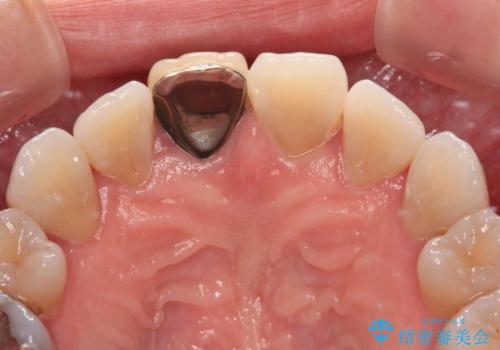

- 結婚式を前に、保険診療での前歯のクラウンが気になるとのことで来院された患者様です。

色合いだけでなく、歯肉の縁が黒くなっていることが分かります。

速やかに仮歯に交換し、オールセラミッククラウンにて補綴することとしました。